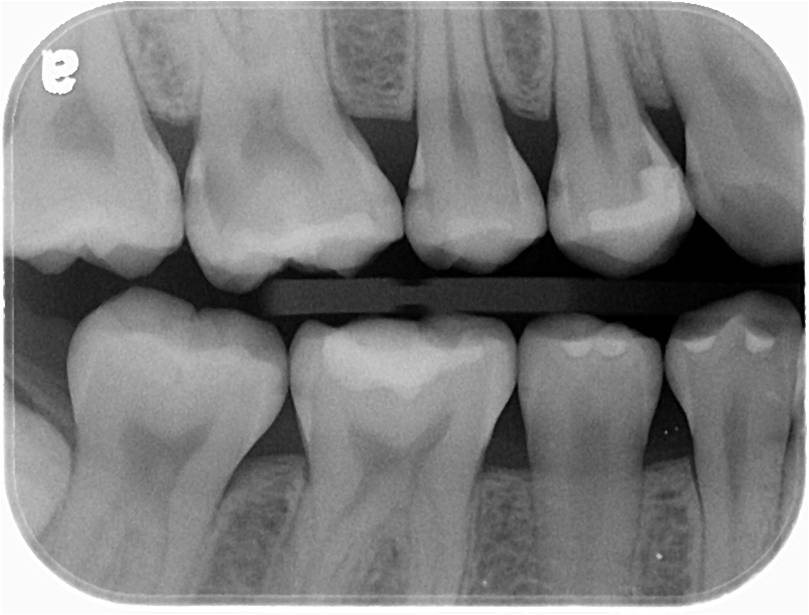

X光可見第一小臼齒至第一大臼齒鄰接面蛀牙